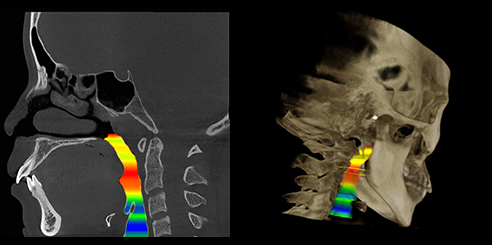

AI + Low-Dose Dental CBCT Technology

- The integrated AI image processor enhances CT quality while reducing radiation exposure.

Consequently, each 3D scan provides superior clarity at a lower dose, ensuring patient safety.

Furthermore, AI+PAN Dental CBCT Imaging enhances precision.

- The system rebuilds panoramic views directly from CBCT data using AI.

- Panoramic auto-focus and multi-layer technology select the best curve automatically.

- Therefore, the final image is cleaner and easier to read.